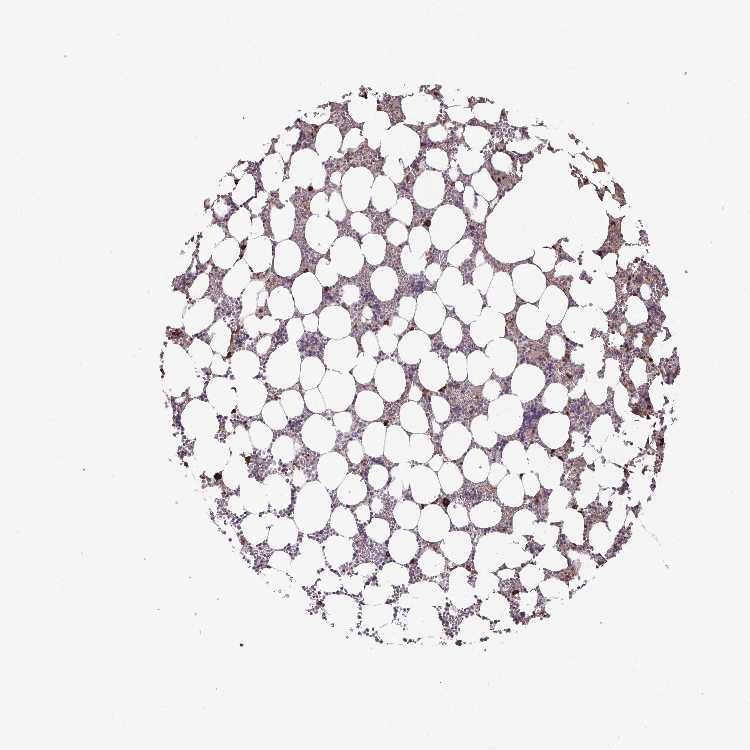

BONE MARROW - Antibody stainingi

Antibody staining in the annotated cell types in the current human tissue is reported as not detected, low, medium, or high, based on conventional immunohistochemistry profiling in selected tissues. This score is based on the combination of the staining intensity and fraction of stained cells.

Each image is clickable and will lead to virtual microscopy that enables deeper exploration of all samples and also displays staining intensity scores, fraction scores and subcellular localization as well as patient and tissue information for each sample.

Antibody HPA054512Antibody HPA059951

Hematopoietic cells MediumLow